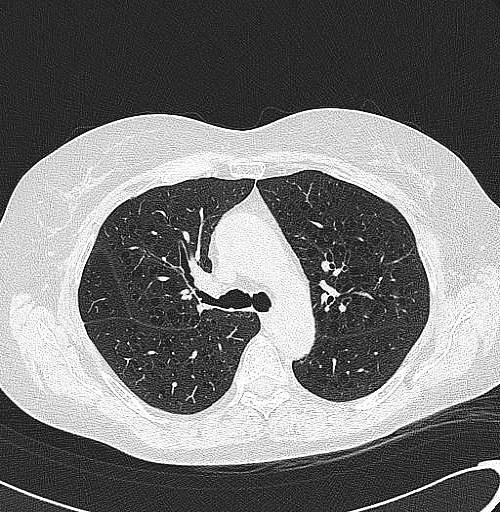

Para ver imagens sobre DPOC, clique aqui.